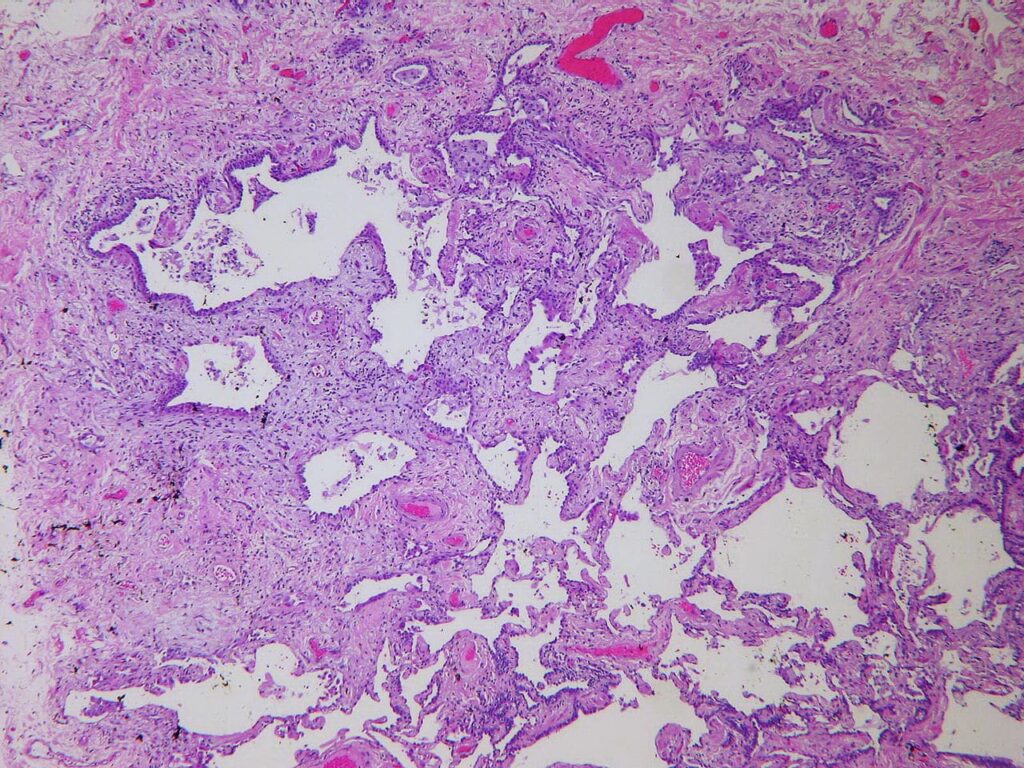

El trabajo fue realizado  por el Dr.Neil Theise y su equipo de investigación en donde utilizando endomicroscopía confocal con láser (pCLE) con fluoresceína como medio de contraste, lograron  demostrar un patrón reticular especializado de fascículos compuestos de fibras colágenas y elásticas que están revestidos por células similares a los fibroblastos, en su interior estas estructuras, están llenas de líquidos que desembocan a capilares linfáticos,

Este patrón se repitió en los principales órganos que están relacionado con la eliminación de los desechos y sustancias en el cuerpo humano, tracto gastrointestinal ,hepatobiliar ,vejiga urinaria,  piel, sistema vascular y cardiorespiratorio.

Según un artículo publicado en Scientific Reports Estas estructuras anatómicas (intersticio) pueden ser importantes en el comportamiento de la mayoría de las enfermedades importantes como la  metástasis del cáncer, edema, y fibrosis.